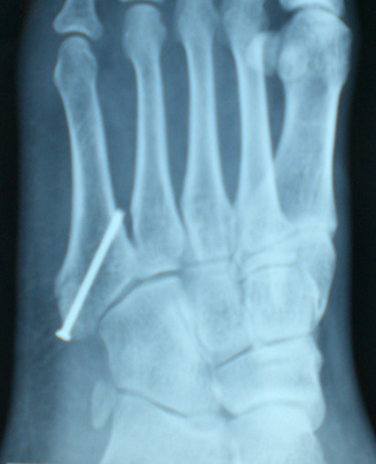

经皮空心钉固定适合于骨折块较大,移位较少,骨质好的患者。具有微创损伤小、不干扰局部的血运、固定牢靠、恢复快等优点。

操作要点:操作要在透视监视下进行,且导针一定要从尖端打入,且在第四、五跖骨间连接以远穿出对侧骨皮质,这样生物力学强度最佳。